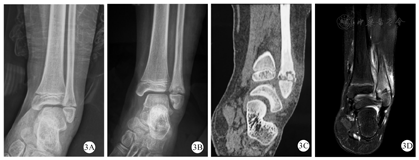

X线是临床上最常用的检查,通常X线在疾病初期无明显改变,随着疾病的进展,X线可显示早期溶骨性病变、硬化、骨扩张或后期呈混合性显像[20,21](图1)。在临床工作中,经验丰富的影像医生才能通过X线检查将CNO与骨肿瘤、感染性骨髓炎鉴别区分。对于无症状的CNO疾病,放射性核素骨显像是常用方法,但因其具有辐射,临床上广泛应用受到限制[22]。MRI是目前最具特异性的影像诊断方法,典型的MRI表现为初期的骨髓水肿,到后期的骨皮质变薄、溶骨性破坏伴硬化(图2、图3、图4)。全身MRI检查在急性炎症期最具有特异性,在MRI可以表现出T1序列低信号和T2序列高信号[21,23]。全身MRI检查在疾病的早期诊断中具有重要的意义,因为它能够在骨溶解、骨硬化之前检测到骨髓水肿和无症状骨病变,并且没有辐射,可用来监测随访骨骼病变的进展演变[24]。(图1、图2、图3、图4中影像学资料均来自同一患者)